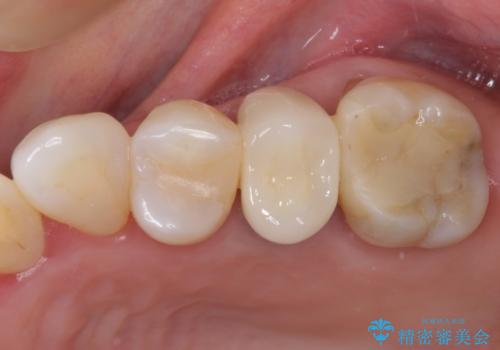

オールセラミッククラウン 欠けてしまった奥歯の治療